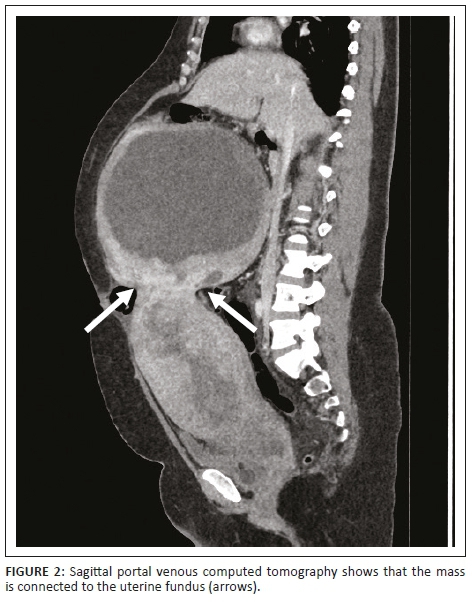

The decision was made to induce labour based on the unclassified proteinuria and the clinical suspicion of possible underlying pre-eclampsia. During the induction of labour, foetal monitoring showed subtle signs of foetal distress, which warranted continuous monitoring, but despite in-patient care and continuous foetal monitoring, there was subsequent intra-uterine foetal demise and the patient delivered a stillborn baby via NVD. Following delivery, the patient's condition deteriorated in the ward, developing a persistent unexplained tachycardia of approximately 150 bpm, a blood pressure of 156/119 mmHg and a serum calcium level well above normal limits (4.25 mmol/L, normal limit is 2.62 mmol/L). Emergent cross-sectional imaging in the form of contrasted CT abdomen showed a large cystic mass with a thick, irregular enhancing wall and septations (Figure 1), which was inseparable from the uterine fundus (Figure 2). In addition, extensive left ovarian and pelvic vein thrombosis (Figure 3) and an enlarged, poorly enhancing left ovary were noted (Figure 4).